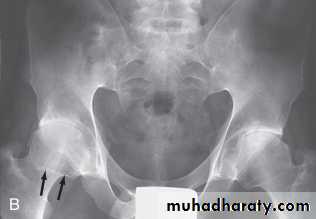

In established AS, radiographs of the sacroiliac joint show irregularity and loss of cortical margins, widening of the joint space and subsequently sclerosis, joint space narrowing and fusion.Lateral thoracolumbar spine Xrays may show anterior ‘squaring’ of vertebrae due to erosion and sclerosis of the anterior corners and periostitis of the waist.

In advanced disease, ossification of the anterior longitudinal ligament and facet joint fusion may also be visible. The combination of these features may result in the typical ‘bamboo’ spine.Erosive changes may be seen in the symphysis pubis, the ischial tuberosities and peripheral joints.